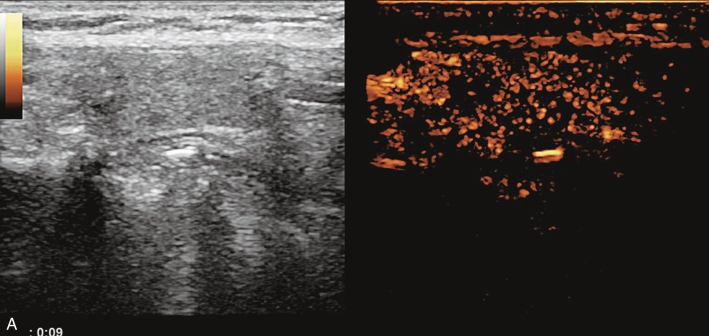

女性,29岁,自觉颈部肿大3天。无发热、咳嗽。

甲状腺右叶中部见一低回声结节,大小约2.0cm×0.9cm×1.7cm,部分边界不清楚,形态不规则,内可见多发点状强回声。CDFI结节内及周边可见较丰富血流信号,见图1-9-7。

图1-9-7 甲状腺髓样癌常规超声声像图

A.甲状腺右叶结节横切面;B.甲状腺右叶结节纵切面;C.甲状腺右叶结节CDFI血流图

甲状腺右叶中部结节超声造影后早于周围组织开始,自周边向中心逐渐增强,达峰时呈不均匀等增强,增强范围较常规超声增大,周边可见不规则环状高增强,结节前方甲状腺被膜连续性中断,之后消退呈明显低增强,见图1-9-8。

图1-9-8 甲状腺髓样癌超声造影图

A.动脉早期;B.达峰时;C.增强晚期

甲状腺右叶中部低回声结节伴有多发钙化,边界不清,形态不规则,血流丰富;超声造影后呈不均匀低增强,周边可见不规则环状高增强结节增强范围较常规超声增大,结节前方甲状腺被膜连续性中断,上述特征均提示恶性。

甲状腺髓样癌超声表现多样,微小结节时与乳头状癌表现类似(特别是伴有钙化时),结节较大时与腺瘤表现类似,内部液化与丰富的血流信号是其鉴别点,边缘分叶状也是其常见的表现类型,超声造影时结节可呈高增强、等增强及稍低增强,周边不规则环状增强及范围扩大可进行良恶性鉴别,本例结节前方甲状腺被膜连续性中断,提示甲状腺前被膜受侵,得到术后病理证实。实验室检查中降钙素、CEA升高对于确诊具有重要意义。